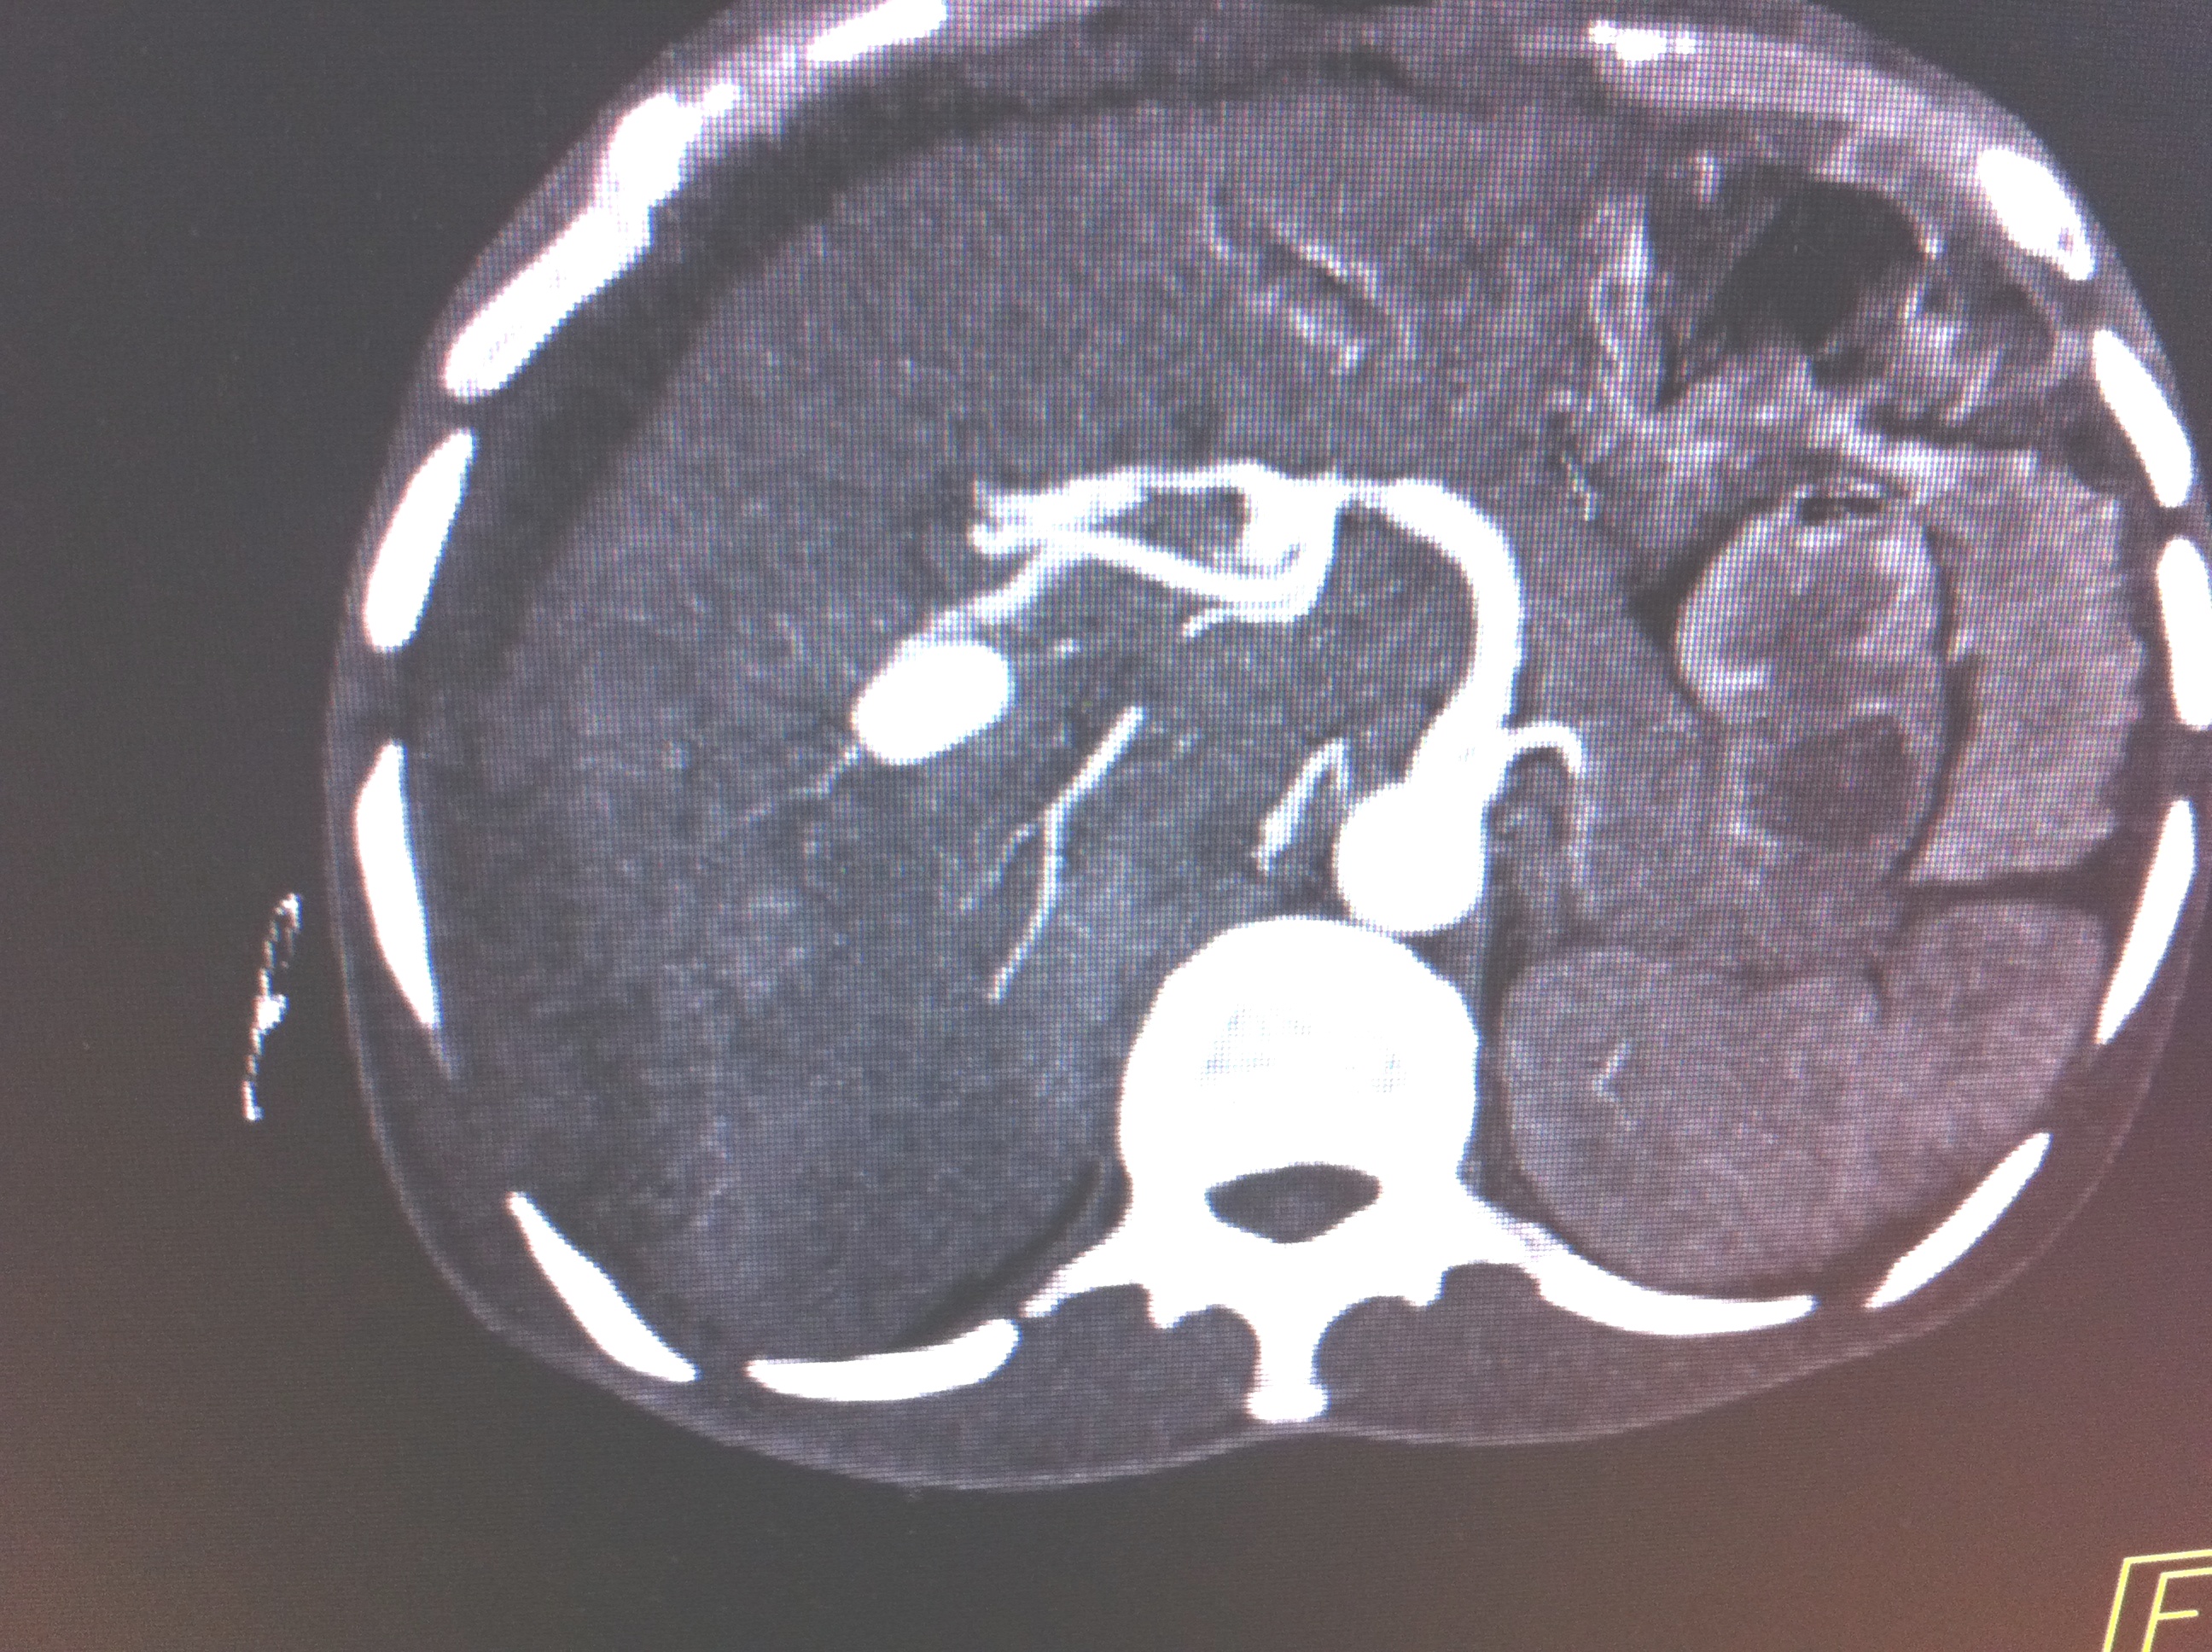

Endoscopic Retrograde Cholangio-Pancreatography (ERCP) has advantage of having bothdiagnostic and therapeutic utility and most common indication for endoscopic sphinterotomyis choledocholithiasis. Therapeutic ERCP is quite often associated with complications, mostcommon being acute pancreatitis followed by bleeding. Most common source of bleedingis small branches of pancreaticoduodenal artery (PDA) which lie close to papilla. We reporta rare case of leaking right hepatic artery pseudoanerysm following clearance of commonbile duct (CBD) stones by ERCP presenting with shock and upper GI bleed.